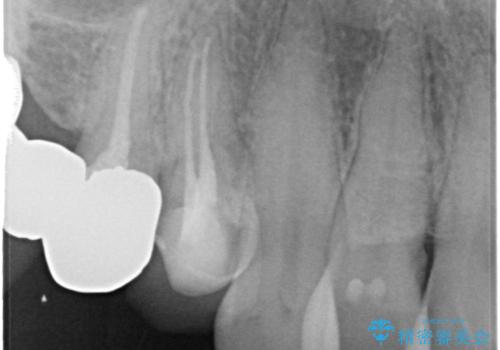

また、左上の犬歯の根の再治療も行いました。

- ジルコニアクラウンスタンダード・仮歯 13.2万円×6 左上3精密根管治療(リトリートメント)・ファイバーコア 12.1万円費用は治療当時の料金となります